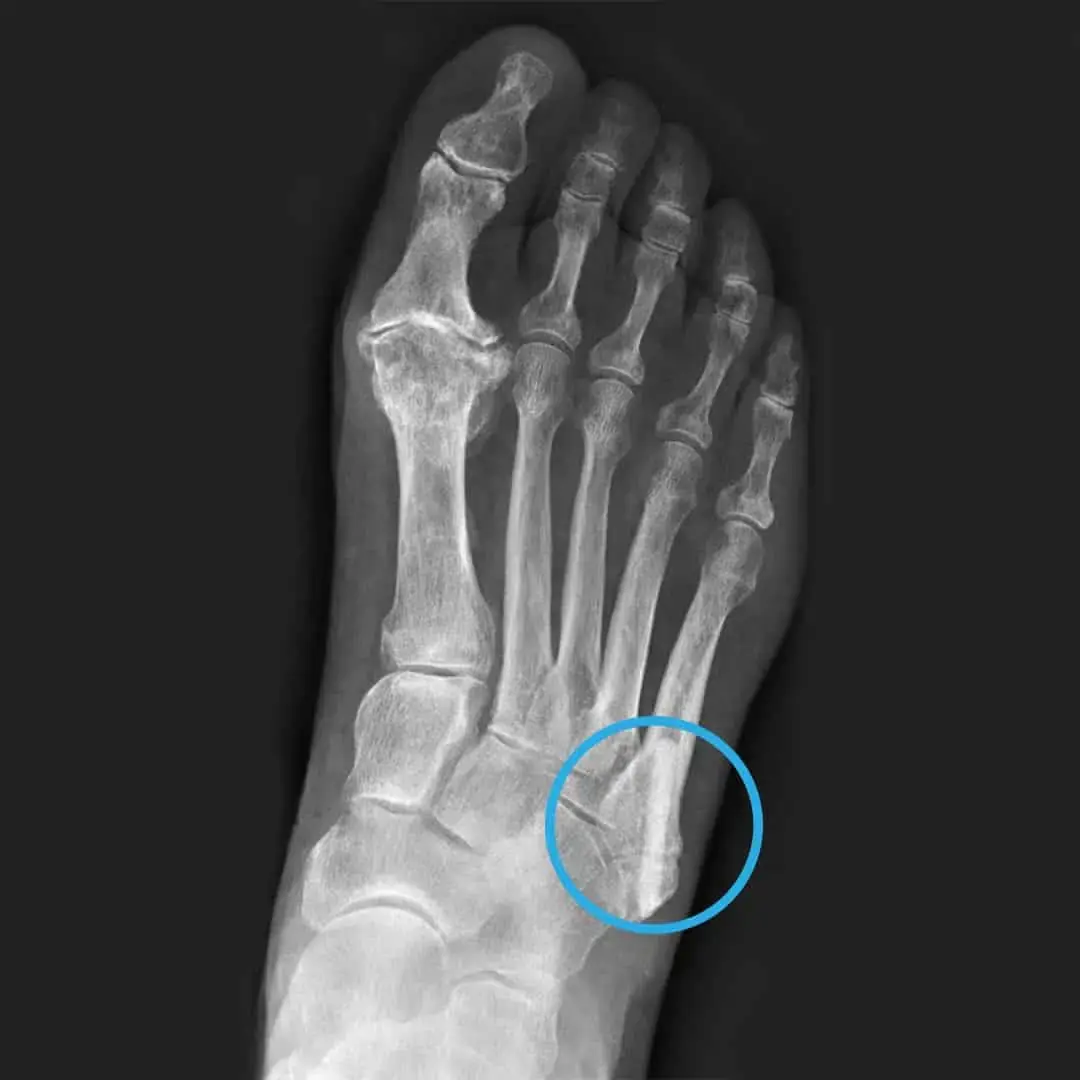

발가락 골절은 흔히 발생하는 상황입니다. 이유는 다양하게 있을 수 있으며, 대표적으로는 실내에서 물건에 부딪히거나 높은 곳에서 떨어지는 등의 사고가 있습니다. 이 외에도 스포츠 활동 중 부상을 당하거나 교통사고 등에서도 발가락 골절이 발생할 수 있습니다. 발가락 골절은 크게 뼈가 완전히 부러진 경우와 뼈에 금만 간 경우로 나눌 수 있으며, 이에 따라 치료 방법과 기간이 다릅니다.

- 깁스 치료: 뼈가 크게 부러진 경우에는 깁스로 고정하는 방법이 일반적입니다.

- 스플린트: 뼈에 금만 간 경우, 즉 미세한 골절의 경우에는 발가락용 스플린트로 치료가 가능합니다.

- 수술: 복합 골절이나 압박 골절의 경우에는 핀을 박는 수술이 필요할 수 있습니다.

- 금속판 사용: 뼈가 조각나거나 비스듬하게 부러진 경우에는 금속판을 덧대어 고정하기도 합니다.